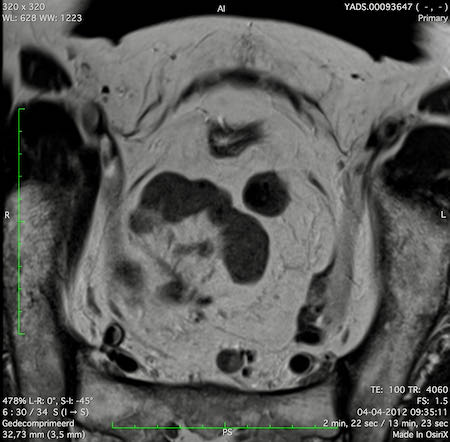

Hình ảnh

Các hình ảnh được cung cấp cho thấy ung thư biểu mô tế bào nhẫn với tình trạng dày lan tỏa thành trực tràng, hình ảnh bia bắn điển hình, và sự xâm lấn mỡ mạc treo trực tràng.